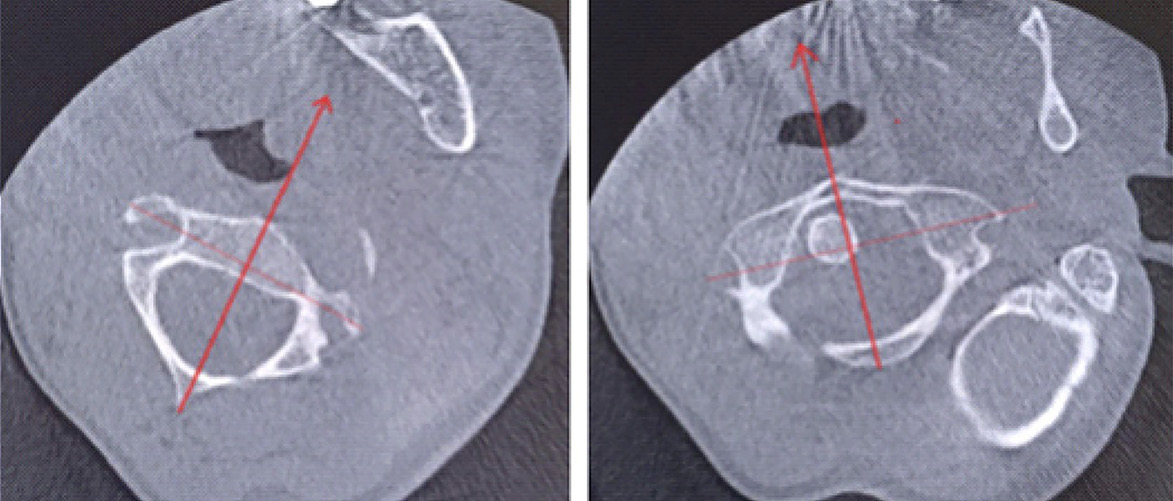

Для оценки ситуации в динамике была проведена КЛКТ, на которой на фоне динамической нерезкости (ребенок был неусидчив) и артефактов от металлоконструкции было отмечено следующее: суставные рентгеновские щели в латеральных атлантоаксиальных суставах: справа – не прослеживается, слева – неравномерно сужена до 0,4 мм в наиболее узком месте (рис. 6). Рентгеновская щель срединного атлантоаксиального сустава в сагиттальной плоскости не прослеживается (рис. 7А), в парасагиттальной плоскости – прослеживается, неравномерная (рис. 7Б). Зубовидный отросток С2 позвонка визуализируется в виде 2 фрагментов, дистальный из которых вместе с передней дужкой С1 позвонка представлен в виде не полностью слитного костного образования. Проксимальный фрагмент, лоцирующийся в проекции верхушки зубовидного отростка С2 позвонка, представлен в виде свободно лежащего отломка с неравномерно склерозированным контуром в проекции диастаза (см. рис. 7). Данная рентгенологическая картина соответствует состоянию после оперативного лечения по поводу травмы шейного отдела позвоночника со стабилизацией металлоостеосинтезом С1–С2 позвонков. Неправильно сросшийся перелом зубовидного отростка С2 позвонка. Частичный анкилоз срединного атлантоаксиального сустава и полный анкилоз правого латерального атлантоаксиального сустава.

Рис. 6. Конусно-лучевая компьютерная томография краниовертебральной области, фронтальный срез на уровне зубовидного отростка С2 позвонка

Рис. 7. Конусно-лучевая компьютерная томография краниовертебральной области, сагиттальный срез (А), парасагиттальный срез (Б). Стрелкой отмечено место анкилоза срединного атлантоаксиального сустава. Двойной стрелкой обозначен свободно лежащий апикальный костный фрагмент зубовидного отростка аксиса